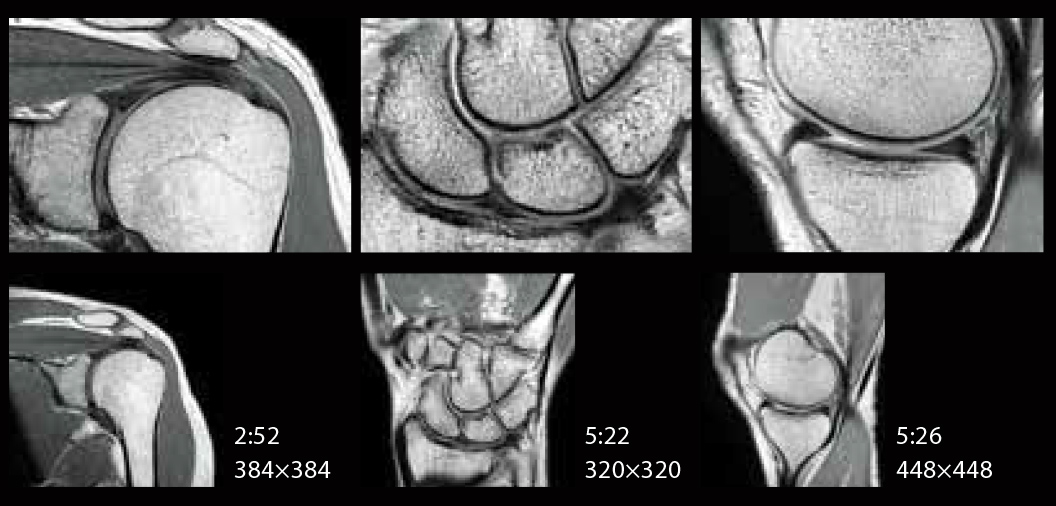

IP-RAPID is high-speed imaging using iterative processing, reducing scan times by up to 60% while maintaining image quality comparable to conventional imaging methods that don't apply IP-RAPID.

IP-RAPID is a technology that can reduce scan time while maintaining image quality.

By combining undersampling and iterative reconstruction, it can be combined with various regions and functions.

SNR and spatial resolution can also be improved while maintaining the scan time.

Value is compared between the following examples